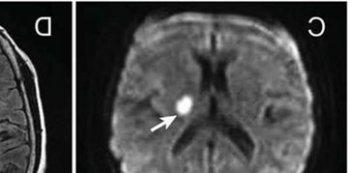

小腦梗塞是一種產生于頭部的病,病發根本原因多見椎-基底動脈出現異常和心源性栓子造成,經核磁共振振(MRI)查驗發覺疾病能夠精確精準定位具備臨床表現??祻椭委熀头婪洞胧┯锌茖W研究精確服藥,防止腦梗塞發作、積極主動地剛開始康復訓練、生活起居訓煉、調節情緒、并發癥的作用修復醫護。

腦梗死這一是一種亞急性的病癥,并且身患這一病癥的致死率都是十分的高的,因此針對腦梗死這一病癥而言更為關鍵的就是說要立即的發覺,立即的醫治。臨床醫學上一般將小腦梗塞分成三種種類:良好型、假腫瘤型和昏迷型,不管哪一型小腦梗塞病發時都是有頭昏、足下垂不穩、惡心干嘔等臨床醫學表型,但后二種除開丘腦候群癥外可以合拼偏癱乃至出現昏迷。